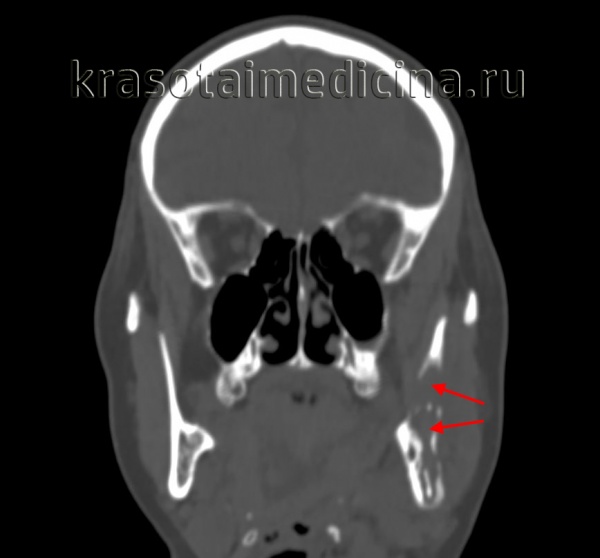

(Слева) На аксиальной МРТ (Т1 ВИ С+ FS) у этой же пациентки определяется равномерное накопление контраста в шванномах нижнего альвеолярного нерва в расширенных нижнечелюстных каналах с обеих сторон.

(Справа) На аксиальной MPT (Т2 ВИ FS) у этой же пациентки определяется гиперинтенсивный сигнал, типичный для шванномы.